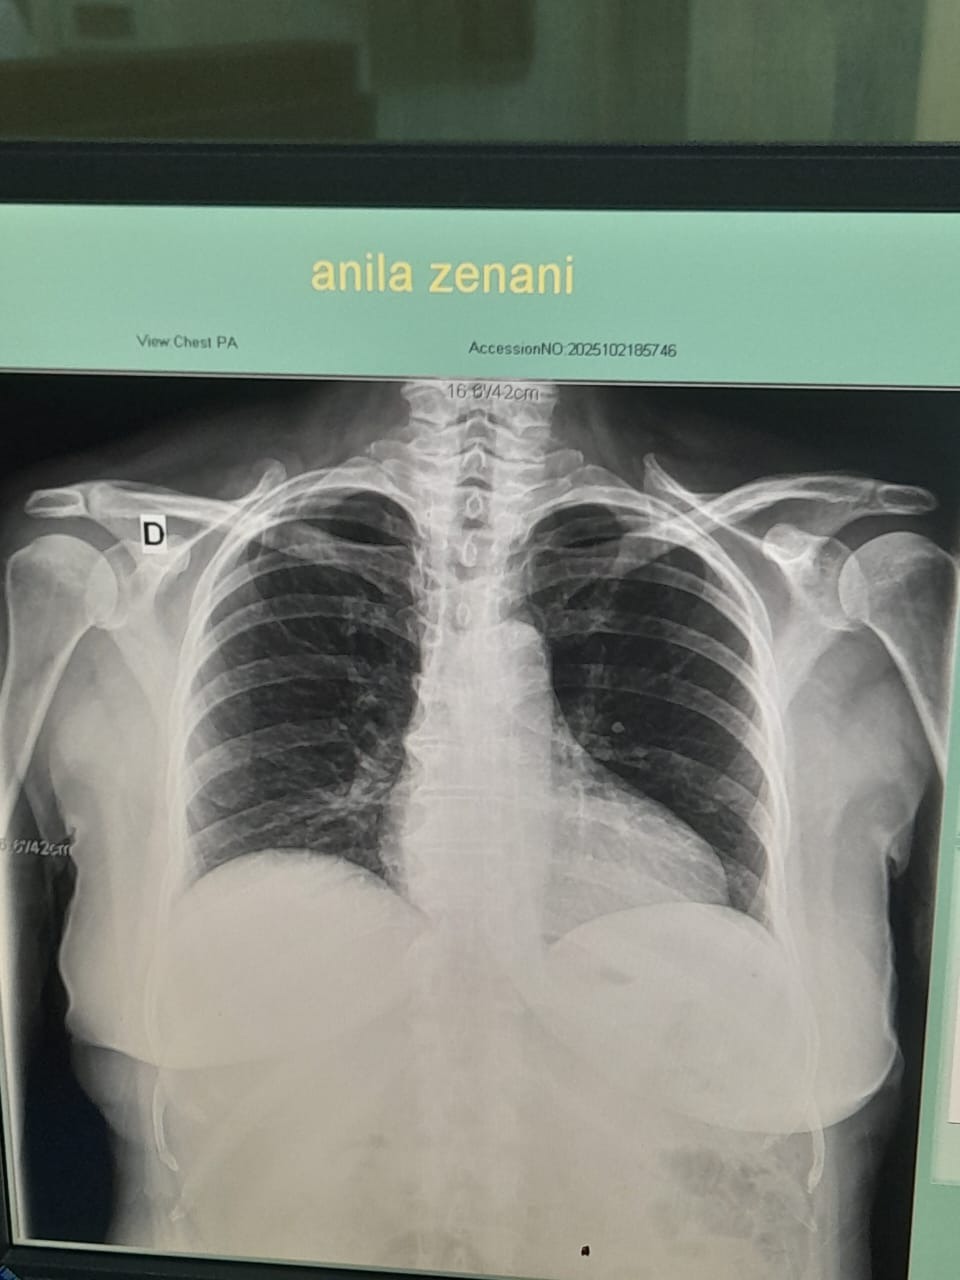

Recently, my mother was diagnosed with breast carcinoma (C50.9 – breast cancer) at the University Hospital “Nënë Tereza” in Tirana. Her medical reports and CT scans show multiple nodules and lymph node involvement, including axillary lymphadenopathy up to 27 mm, retroareolar masses, and lesions in both breasts that require immediate and continued oncological treatment.

Doctors have also identified hyperplastic and hypertrophic changes in several organs, and she has been undergoing detailed imaging, laboratory exams, and oncology consultations. The oncologist, Dr. Sabo Ademi, and radiologist Dr. Eni Mehmeti, both confirmed the need for urgent follow-up treatments and possible biopsy and therapy due to the spread of nodules and lymphatic changes.